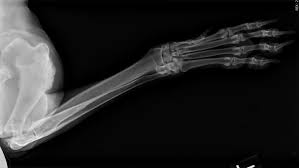

Bone cancer is a common cancer in dogs, especially in large and giant breeds. Amputation will restore quality of life, and in many cases, actually extend it, since dogs with severe pain from bone cancer are often euthanized at an early stage to end their suffering. If the cancer develops in the legs, as it does in most cases, the usual course of treatment is amputation. Primary refers to cancer that starts in the bone versus spreading (metastasizing) into the bone from somewhere. The conventional treatment of choice for canine bone cancer that occurs in the limbs is surgery (amputation of the affected limb). Still, in contrast to humans, the most common form of bone cancer seen in dogs is osteosarcoma, according to a study in the u.s. Untreated bone pain may interfere with your ability to battle the disease and reduce your quality of life. Let's talk about one of the most occurring bone cancer in dogs.in dogs, bone cancer also can occur as a primary or metastatic disease. Many guardians are surprised to find out just how many tools veterinarians have to help with their dog's pain. Because there is an overlap of symptoms, it is often difficult to distinguish whether swelling and pain within a dog or cat's toe is due to a tumor or infection. These surgeries have proved valuable in people with terminal cancer and poorly responsive pain. Intestinal or pelvic obstruction, bone pain from a primary or metastatic tumor and oral ulceration are a few of the causes of severe pain in cancer patients. Limb sparing surgery is a procedure that replaces a diseased area of bone with a metal implant, or bone graft from another dog (allograft) , or a combination of bone graft and metal implant (allo prosthetic.